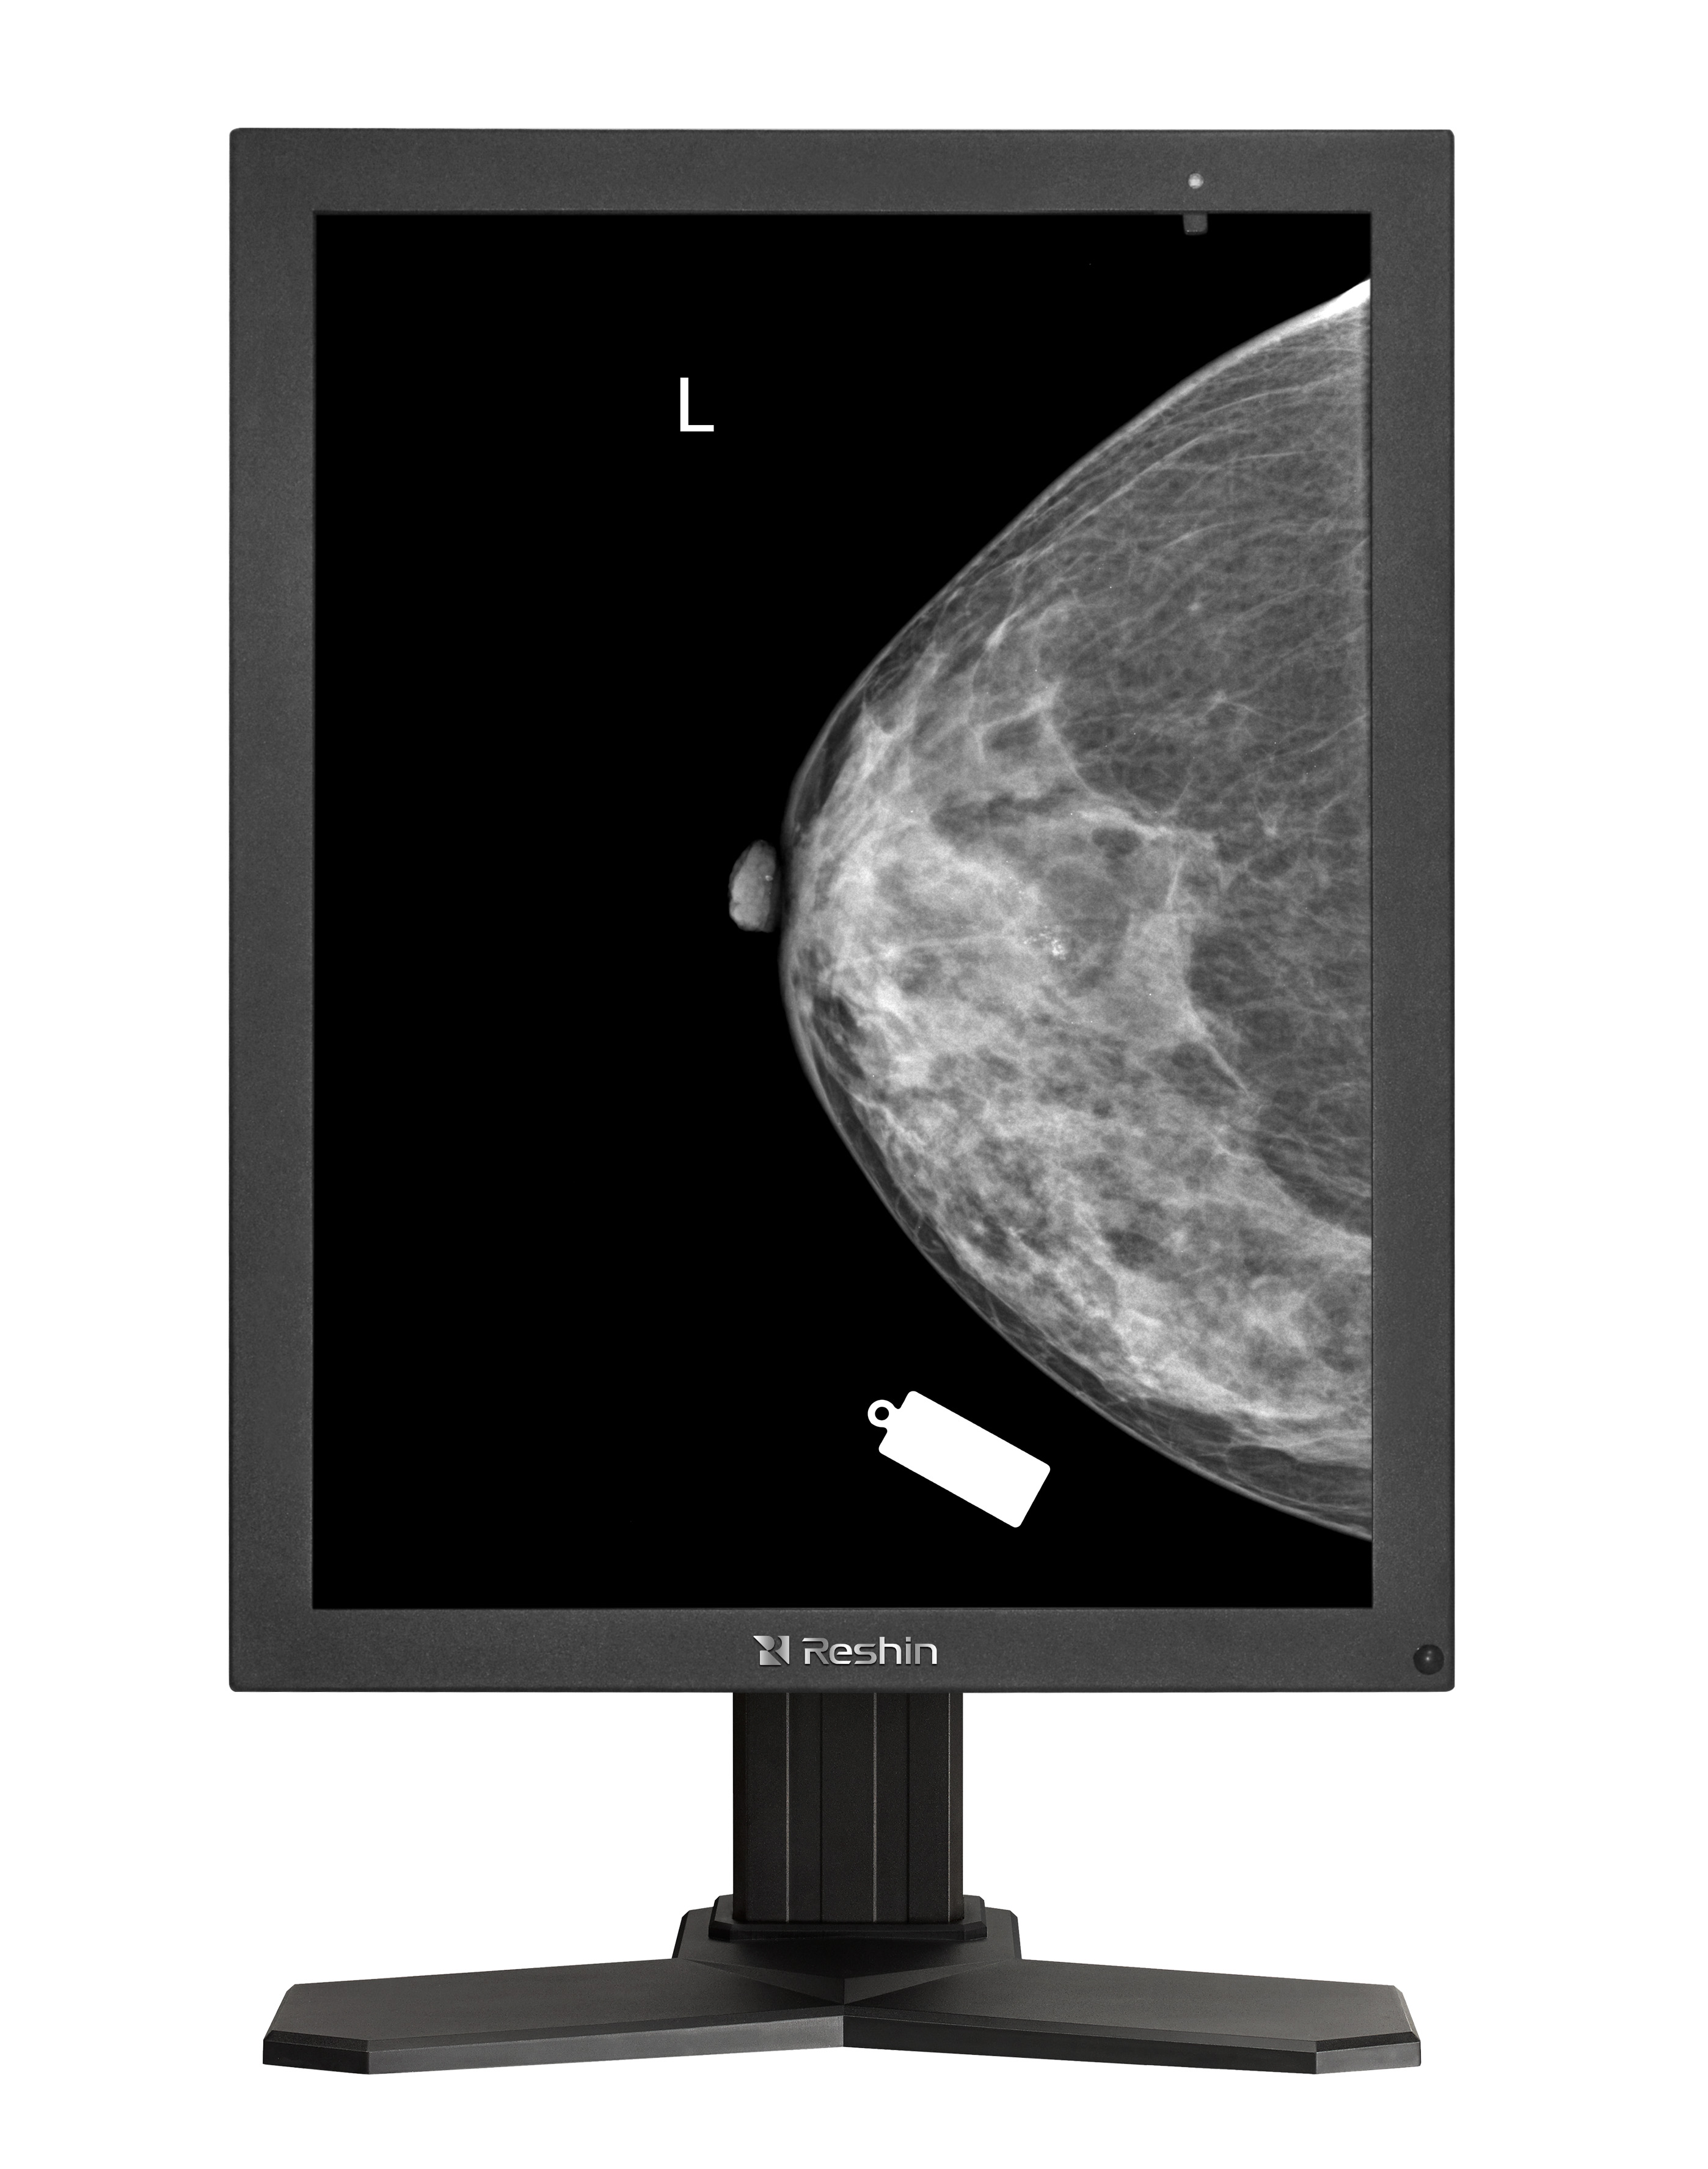

睿显灰阶显示器

这种差异源于医疗影像的特殊需求:X 光、CT、MRI 等设备生成的图像本质上是灰度图像,病灶与正常组织的密度差异往往通过细微的灰阶变化体现。例如,肺部 CT 影像中 0.1% 的灰度差异可能对应早期结节的检出,医用灰阶显示器的高密度灰阶输出能力,能将这种细微差异转化为肉眼可辨的影像层次,而普通显示器会因灰阶断层导致细节丢失,直接影响诊断准确性。

普通显示器的色彩校准以视觉舒适度和娱乐体验为核心,厂商通常通过 sRGB 或 Adobe RGB 色域增强色彩饱和度,适合观看电影、设计绘图等场景。但在医疗场景中,色彩偏差可能导致误诊 —— 例如,乳腺钼靶影像的伪彩色显示可能掩盖钙化点的真实灰度,影响医生判断。